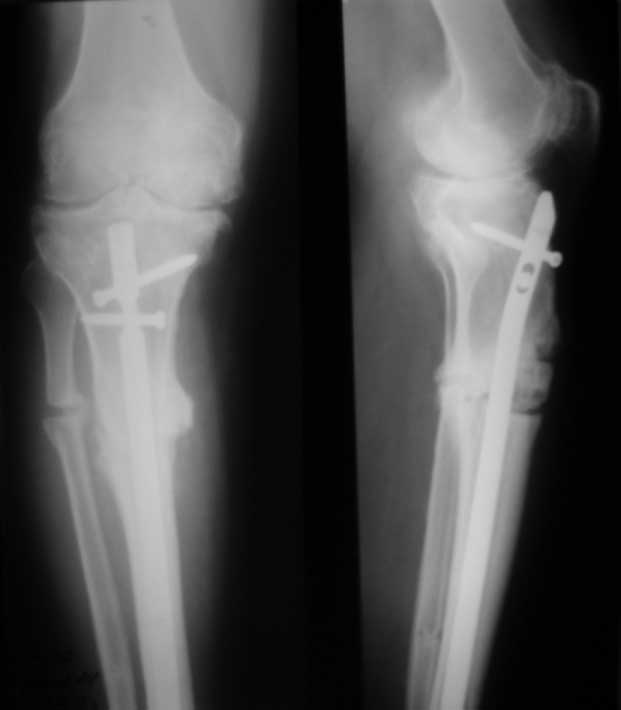

Уважаемые коллеги. Пациент 8 мес после операции ТКА, в анамнезе – неправильно сросшийся перелом голени, коррекция оси (снимки прилагаются. В настоящее время имеется разгибательная контрактура 10/5/0, на операционном столе было 90/0/5, на момент выписки движения 50/0/0 в надежде на дальнейшую разработку. До эндопротезирования 40/10/0. Глубокая инфекция исключена. Ротация бедренного компонента в норме (по КТ).